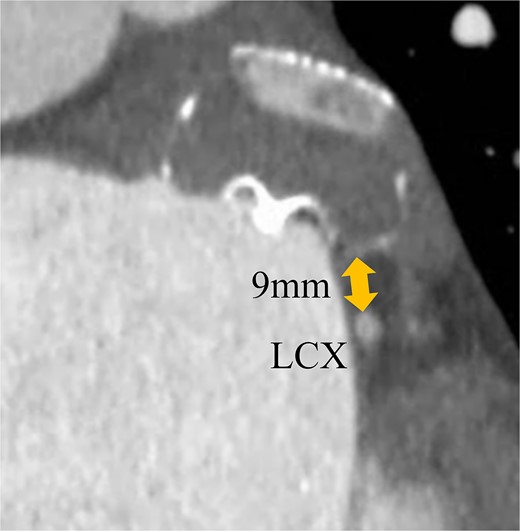

A 74-year-old male with a history of chronic atrial fibrillation (AF) for over 10 years, cardioembolic stroke, and cerebral hemorrhage, who had undergone LAA closure using the WATCHMAN device 1 year prior, was admitted after a follow-up contrast-enhanced CT scan revealed a 25-mm intracardiac mass in the right atrium (RA) (Fig. 1). After the WATCHMAN implantation, the patient was initially on direct oral anticoagulant (DOAC) but switched to dual antiplatelet therapy (DAPT) following the placement of a drug-eluting stent during percutaneous coronary intervention performed 9 months later. Transthoracic echocardiography revealed a left ventricular ejection fraction of 61% and a right atrial mass measuring 17 × 19 mm with slight mobility (Fig. 2). Despite anticoagulation therapy with heparin, the right atrial mass did not reduce in size. The patient decided to undertake surgical removal of the mass due to the potential risks of tumor or embolization. Additionally, contrast-enhanced CT showed a peri-device leak around the WATCHMAN device (Fig. 3). Considering the patient’s history of cerebral hemorrhage and the anticipated future cessation of anticoagulation therapy, we determined to perform WATCHMAN device explantation and LAA closure. Preoperative contrast-enhanced CT showed no thrombi attached to the WATCHMAN device and sufficient distance from the left circumflex artery (LCX) and the device (Fig. 4). We planned to remove the device by incising from the outside surface of the LAA. The Maze procedure was not performed because it was considered less effective due to the patient’s history of AF lasting more than 20 years and the presence of flat f-waves in lead V1 on the 12-lead electrocardiogram.

Preoperative enhanced computed tomography imaging showing the distance between the WATCHMAN device and the LCX was ~9 mm.

However, primary endocardial suture closure of the LAA has a re-opening risk rate of 36% [2]. There might be a similar risk of re-opening with the exclusion of the LAA using a bovine pericardial patch. Consequently, we have adopted the external approach that involves removing the LAA along with the WATCHMAN device. This technique offers the advantages of being performed without an extra incision at the right side of the left atrium, enabling the entire resection of the LAA, and the risk of thrombus formation is reduced significantly. However, in cases where thrombi are adherent to the device, there is a risk of thrombus dislodging into the cardiac chamber. When the device is close to the LCX, there is a risk of arterial injury. Under these circumstances, this approach is inappropriate. Surgeons are required to evaluate the position, size, and thrombus to select appropriate methods.